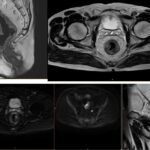

Imágenes de resonancia magnética